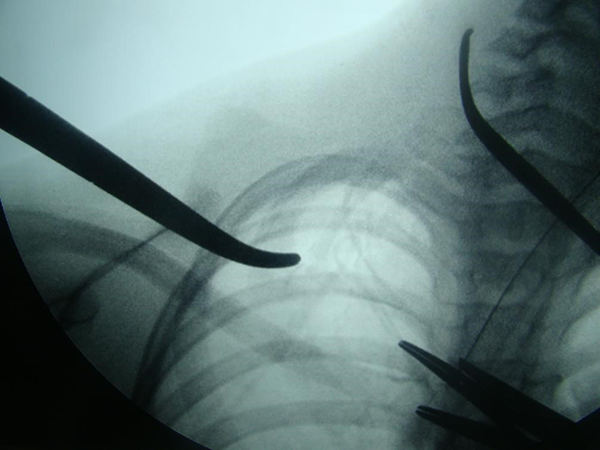

Se realiza radioscopia para identificar trayecto de difícil interpretación por el tipo de tejido cartilaginoso (foto 4) y resección ósea y neurolisis de las raíces del plexo braquial (foto 5).

Foto 4 . Radioscopia operatoria. Se visualiza con poca intensidad costilla cervical;

la pinza central marca inicio costilla cervical ( poco visible por tejido cartilaginoso)